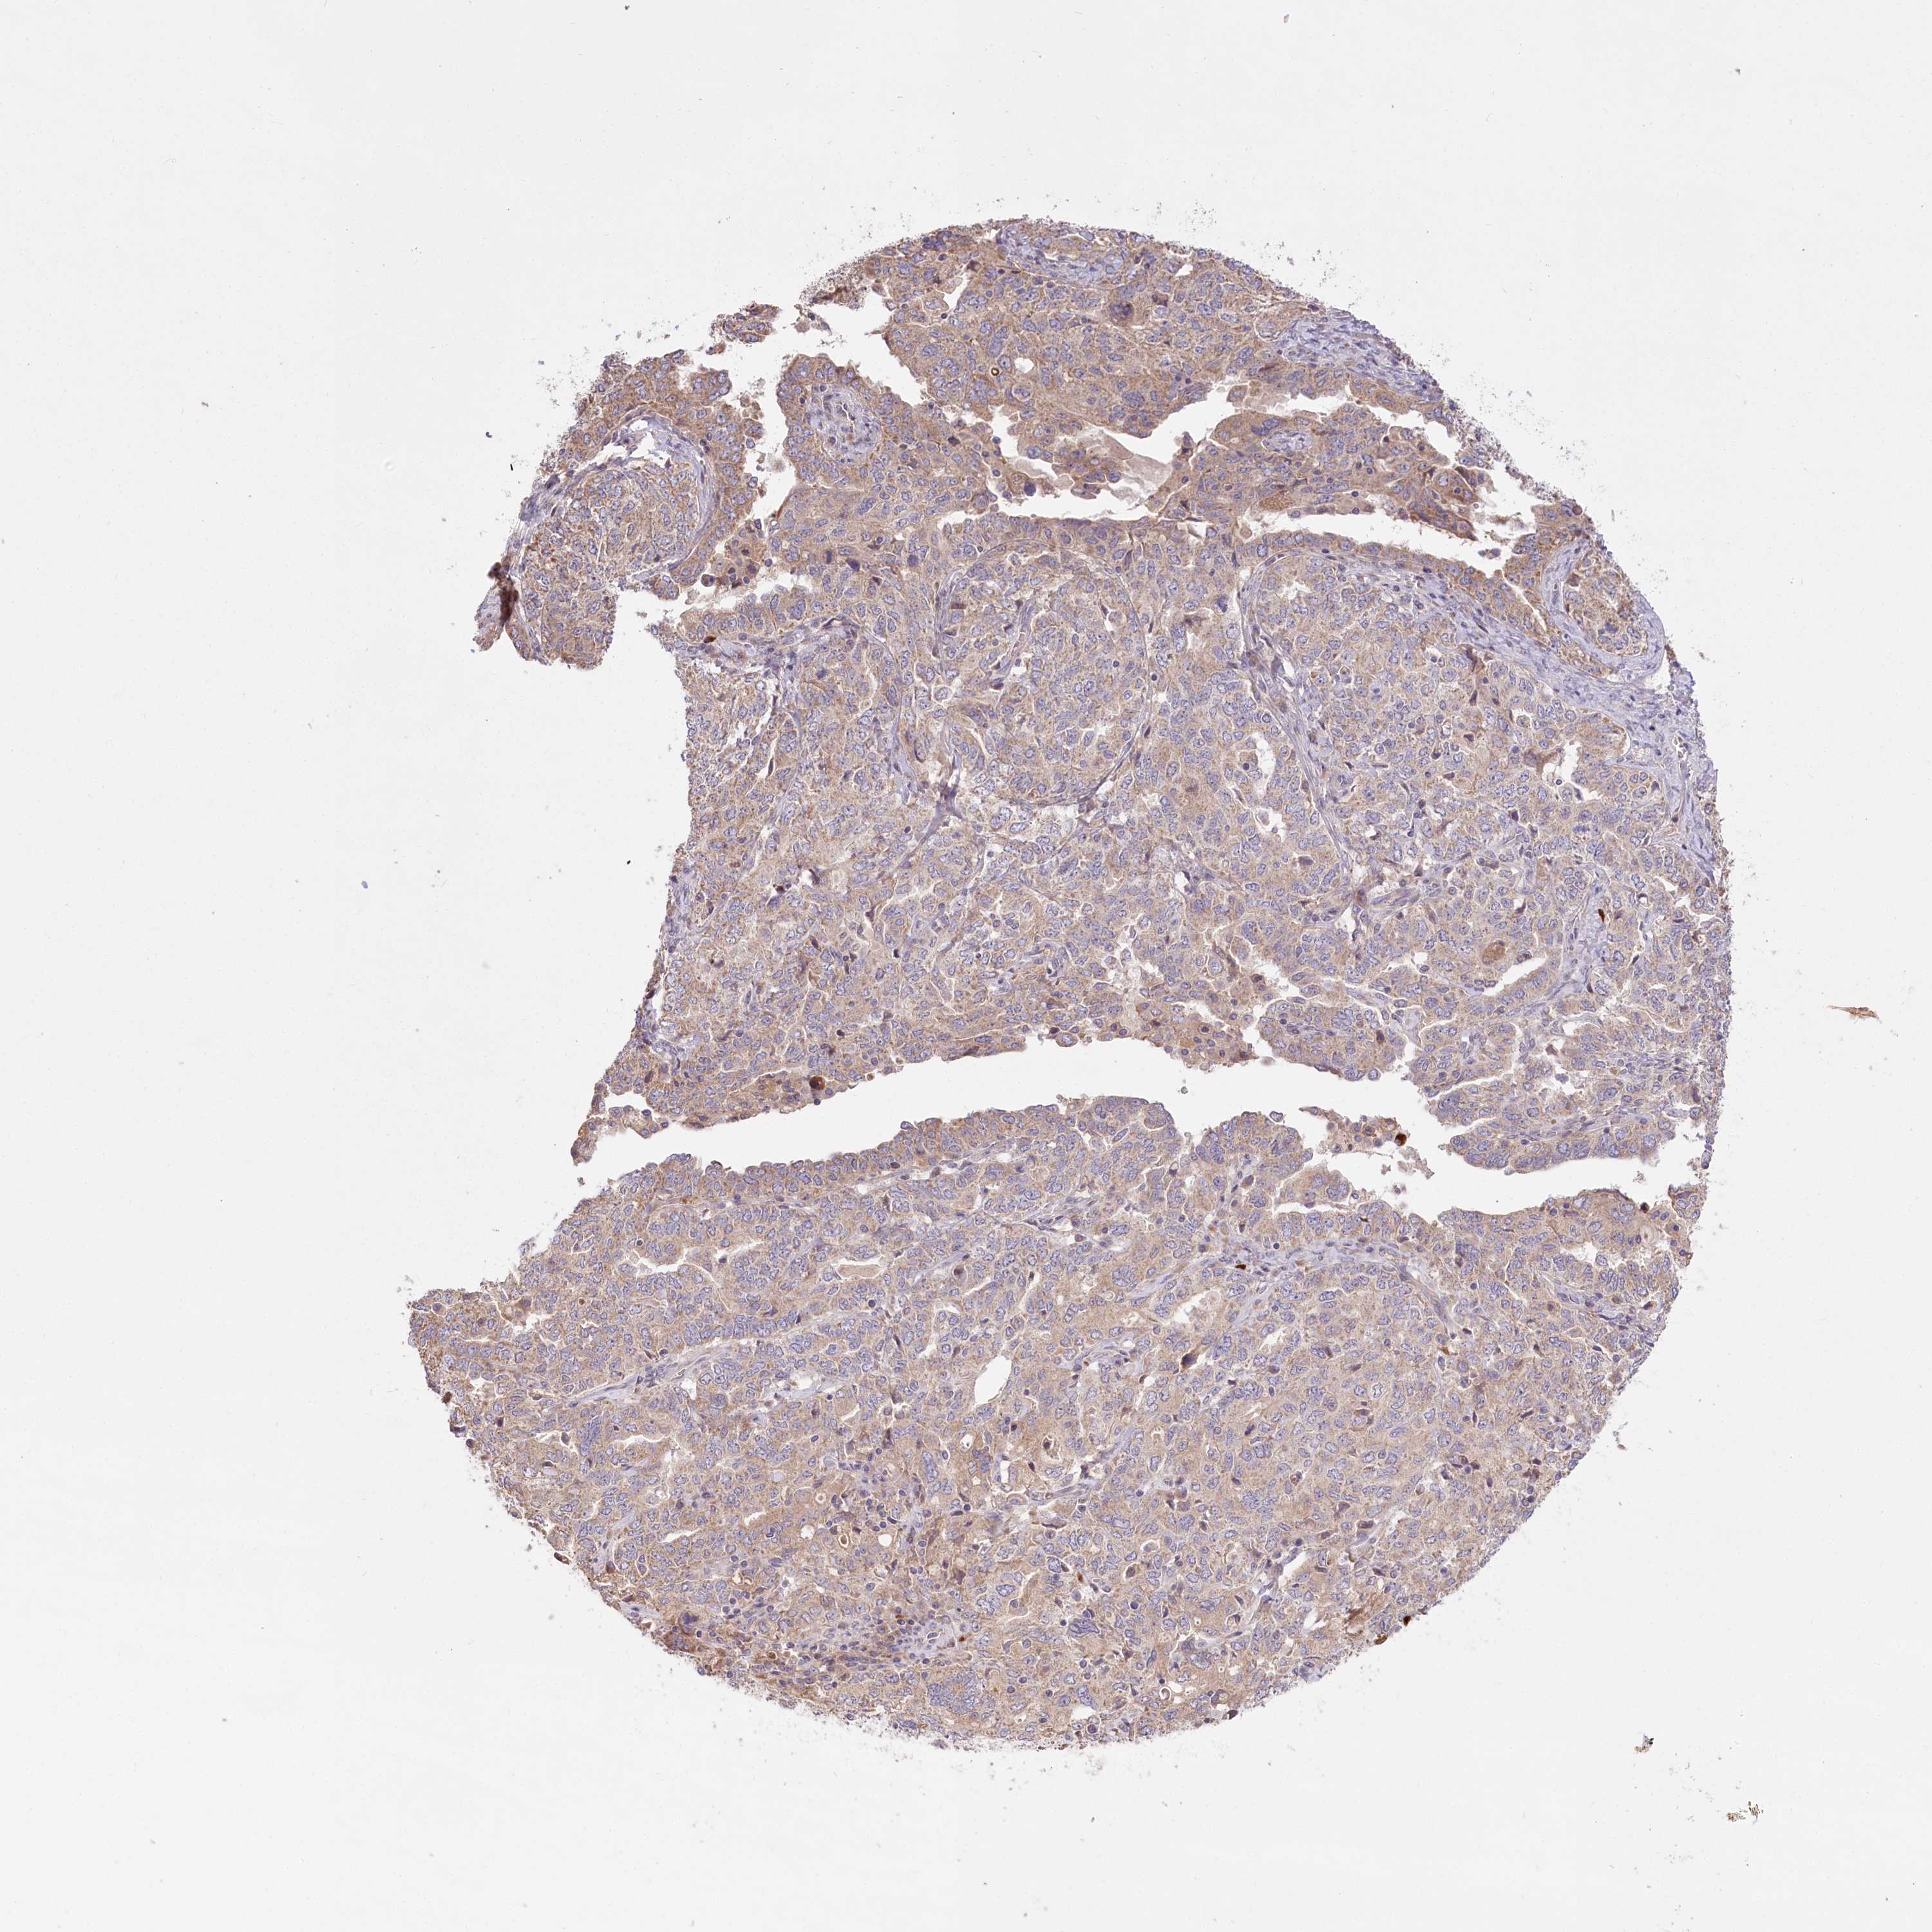

OVARIAN CANCER - Protein expressioni

A mouse-over function shows sample information and annotation data. Click on an image to view it in a full screen mode. Samples can be filtered based on level of antibody staining by selecting one or several of the following categories: high, medium, low and not detected. The assay and annotation is described here.

Note that samples used for immunohistochemistry by the Human Protein Atlas do not correspond to samples in the TCGA dataset.

Antibody stainingi

Antibody staining in the annotated cell types in the current human tissue is reported as not detected, low, medium, or high, based on conventional immunohistochemistry profiling in selected tissues. This score is based on the combination of the staining intensity and fraction of stained cells.

Each image is clickable and will lead to virtual microscopy that enables deeper exploration of all samples and also displays staining intensity scores, fraction scores and subcellular localization as well as patient and tissue information for each sample.

Antibody HPA038035

Antibody HPA038036

Cystadenocarcinoma, serous, NOS

Carcinoma, endometroid

Cystadenocarcinoma, mucinous, NOS

Carcinoma, NOS